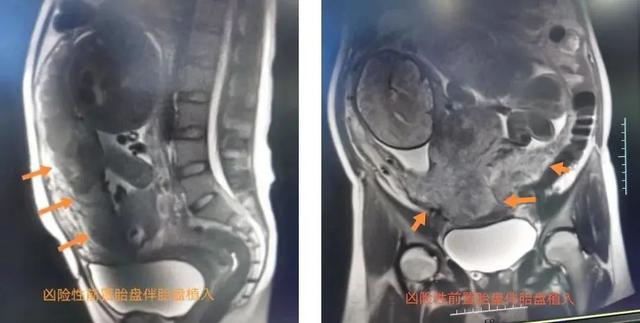

近日,怀孕36周的孕妇嘎女士因间断阴道流血来到西藏自治区人民医院就诊。经核磁共振及彩超检查,医生判断嘎女士是“前置胎盘合并胎盘植入”,分娩时极易引起术中及术后大出血,威胁母婴生命安全。

一般情况下,凶险性前置胎盘孕妇需以剖宫产结束妊娠,而伴有胎盘植入的产妇在手术中极有可能出现大出血,死亡率高达7%,有时甚至需要切除子宫以挽救孕妇生命,子宫切除率更是超过50%。